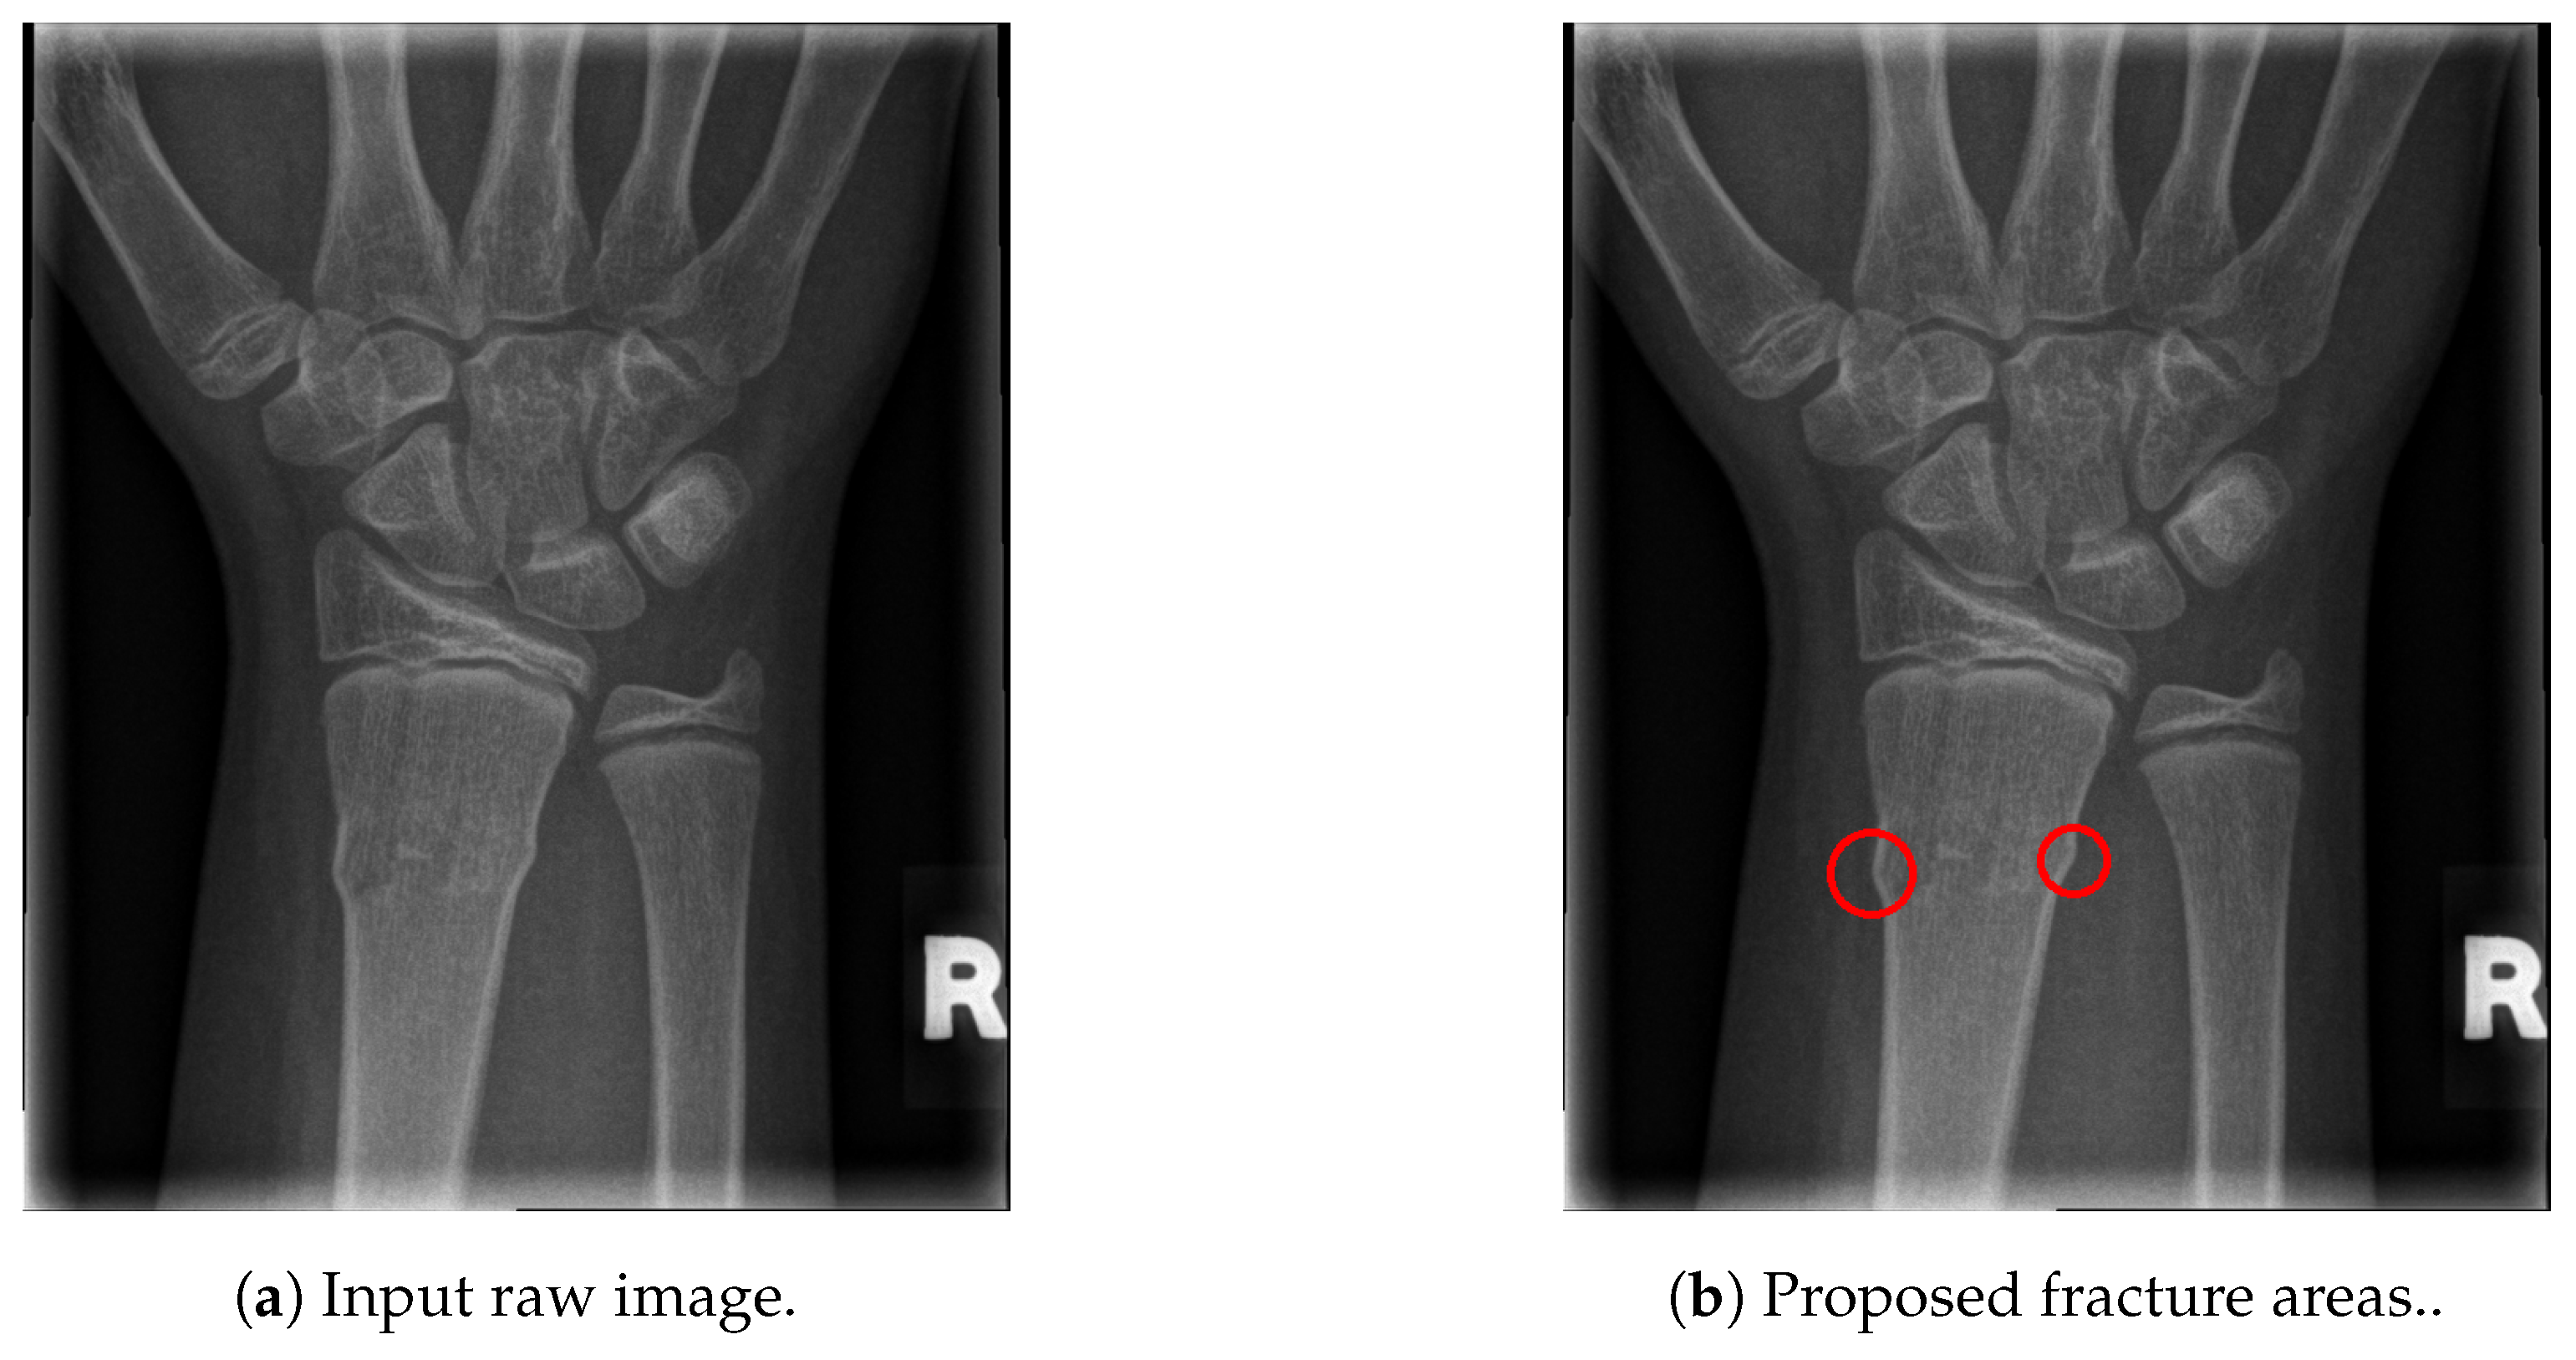

The final fracture detection and localisation results are shown in Figure 12, Figure 13, Figure 14 and Figure 15 (denoted by blue lines). Figure 12 and Figure 13 show two peaks which represent potential fractures. The critical fracture area is marked in the X-ray image by a red circle (at the centre of which is the coordinate of the highest peak, with radius being defined by the width of the area), as shown in Figure 16.

Figure 16.

Fracture area detection.

As can be seen, the proposed method was shown to be efficient, not only in detecting the fractures in the images (flagging the images as either containing fractures or fracture-free), but also precisely localising the position and the size of the region with the fracture. This can be used to assist medical staff to consider only the images with fractures and to direct their attention to specific regions of interests containing demanding fractures.